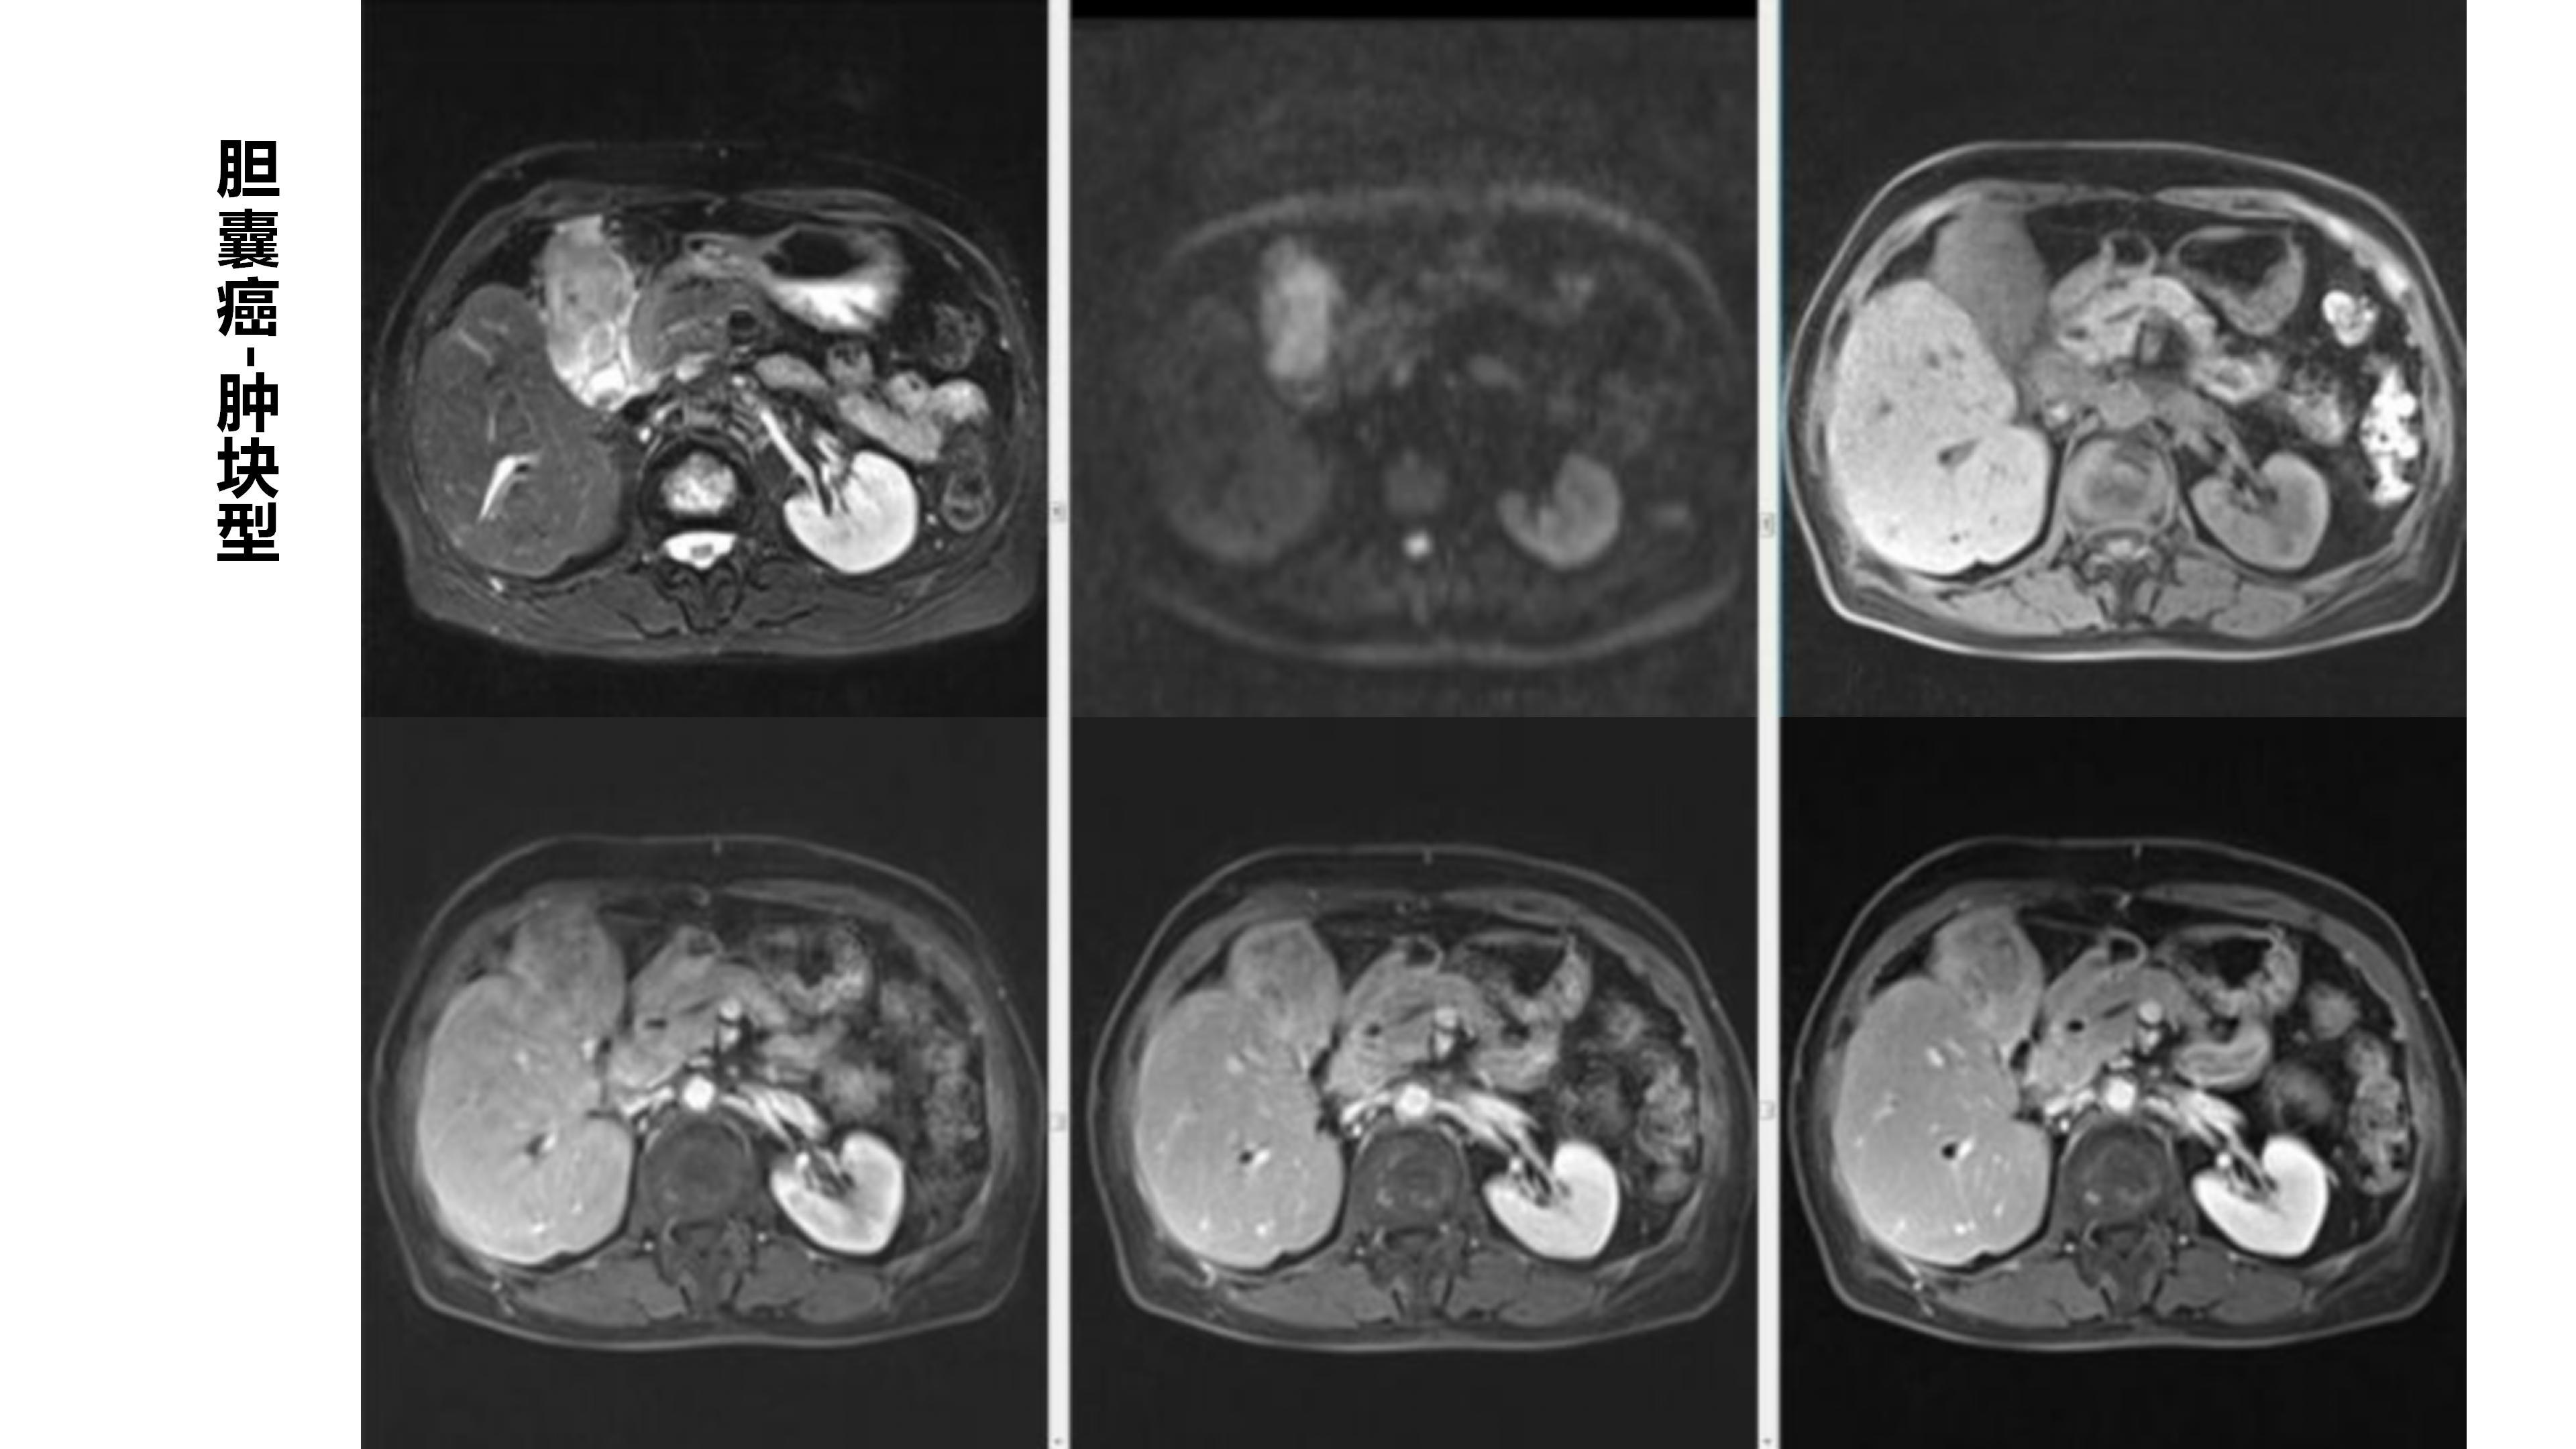

胆囊癌-鼎湖社群读片病例